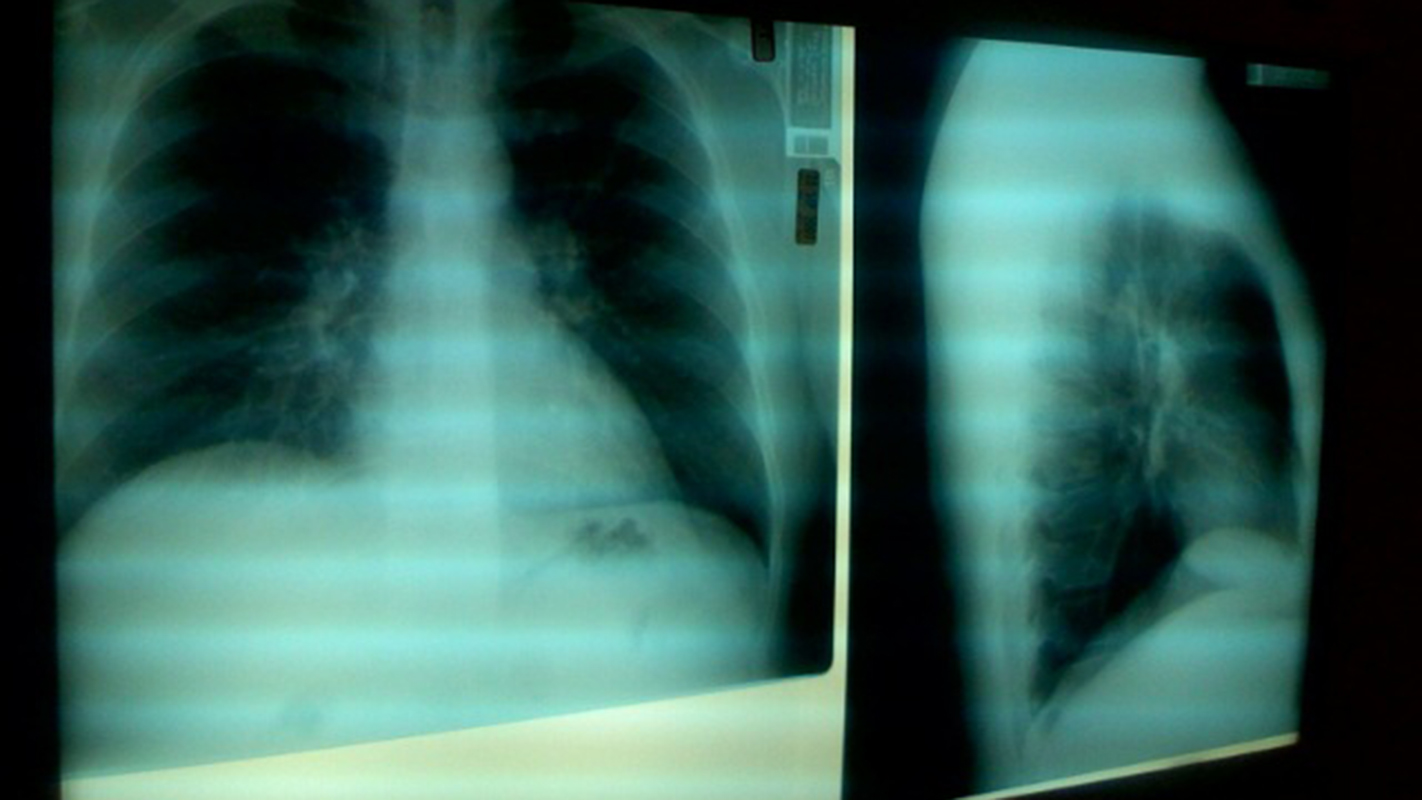

北卡罗莱纳州立大学的研究人员开发了一种有效的算法,可以解释呼吸困难患者的喘息声,为医疗服务提供者提供有关肺部状况的信息。这项研究是一个更大、正在进行的项目的一部分,该项目旨在开发可穿戴智能医疗传感器,用于监测、收集和解读个人健康数据。

“协助的研究人员开发了可穿戴传感器,这些传感器由患者的身体提供动力,可以监测患者呼吸的声音,”NC州的电脑工程教授Krim表示,在工作中的一篇论文中的一篇论文的高级作者。“现在我们开发了一种可以评估喘息声音的开始时间,音高和幅度(或体积)的算法,以提供有关肺部状况的医疗保健专业人员信息。反过来,这些信息可以用来帮助医生做出关于诊断和治疗的更明智的决定。“

KRIM解释说,喘息的声音因问题在肺部和问题的严重程度而异。该算法占这些差异,以告诉医生究竟发生了什么。“无论患者的物理尺寸如何,算法是有效的,”Krim表示,“并且能够处理与呼吸模式相关的变异性和复杂性。”